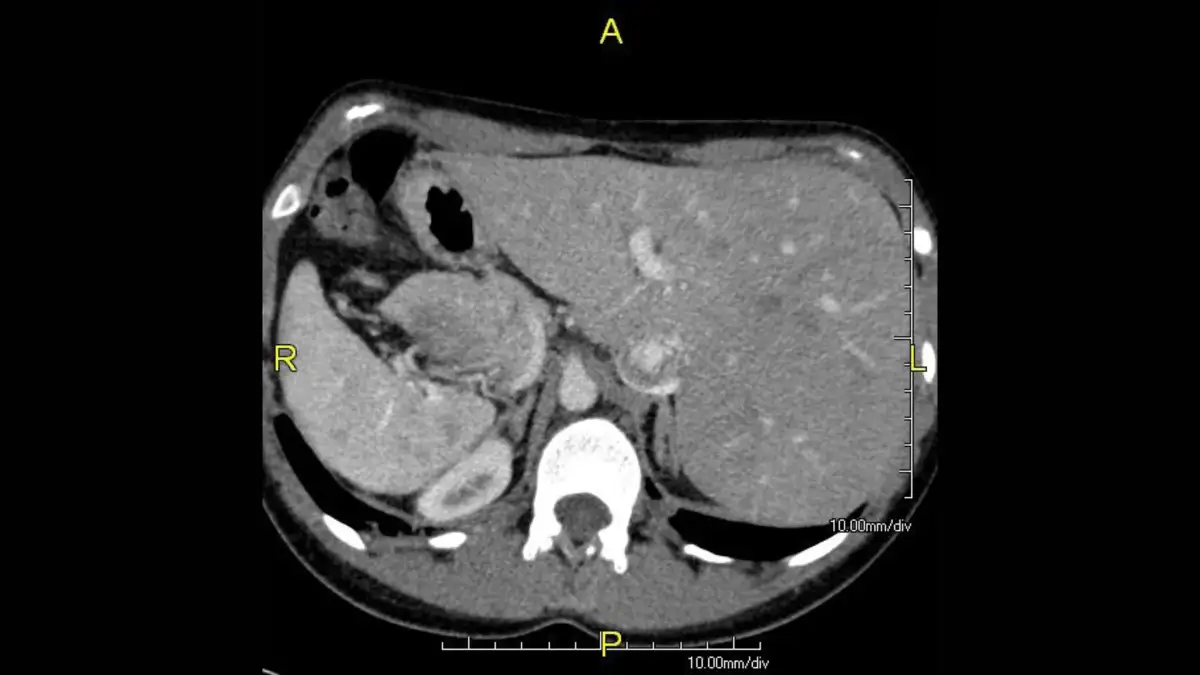

In a reality where biology occasionally veers off its presumed course, Randy Foye, a former NBA point guard, lives with situs inversus. This condition, a rare congenital anomaly, dictates that his major visceral organs are positioned in a mirrored fashion to the typical human anatomy. His heart, rather than residing on the left, is situated on the right side of his chest, with his liver also taking up a leftward position.

Situs inversus affects approximately 1 in every 10,000 births. It represents a significant deviation from the standard organ arrangement, known as situs solitus. The precise causative factor for this genetic mutation remains an enigma, with scientists acknowledging its presence without fully comprehending its origin. While some cases of situs inversus might coincide with other health issues, such as congenital heart disease or primary ciliary dyskinesia, many individuals experience no related complications.

The condition is often discovered incidentally, sometimes during routine medical examinations like listening to a heartbeat. For those with situs inversus, particularly athletes, wearing identifying medical alerts, such as MedicAlert bracelets, is often advised to inform medical professionals of their unique internal architecture in emergencies.